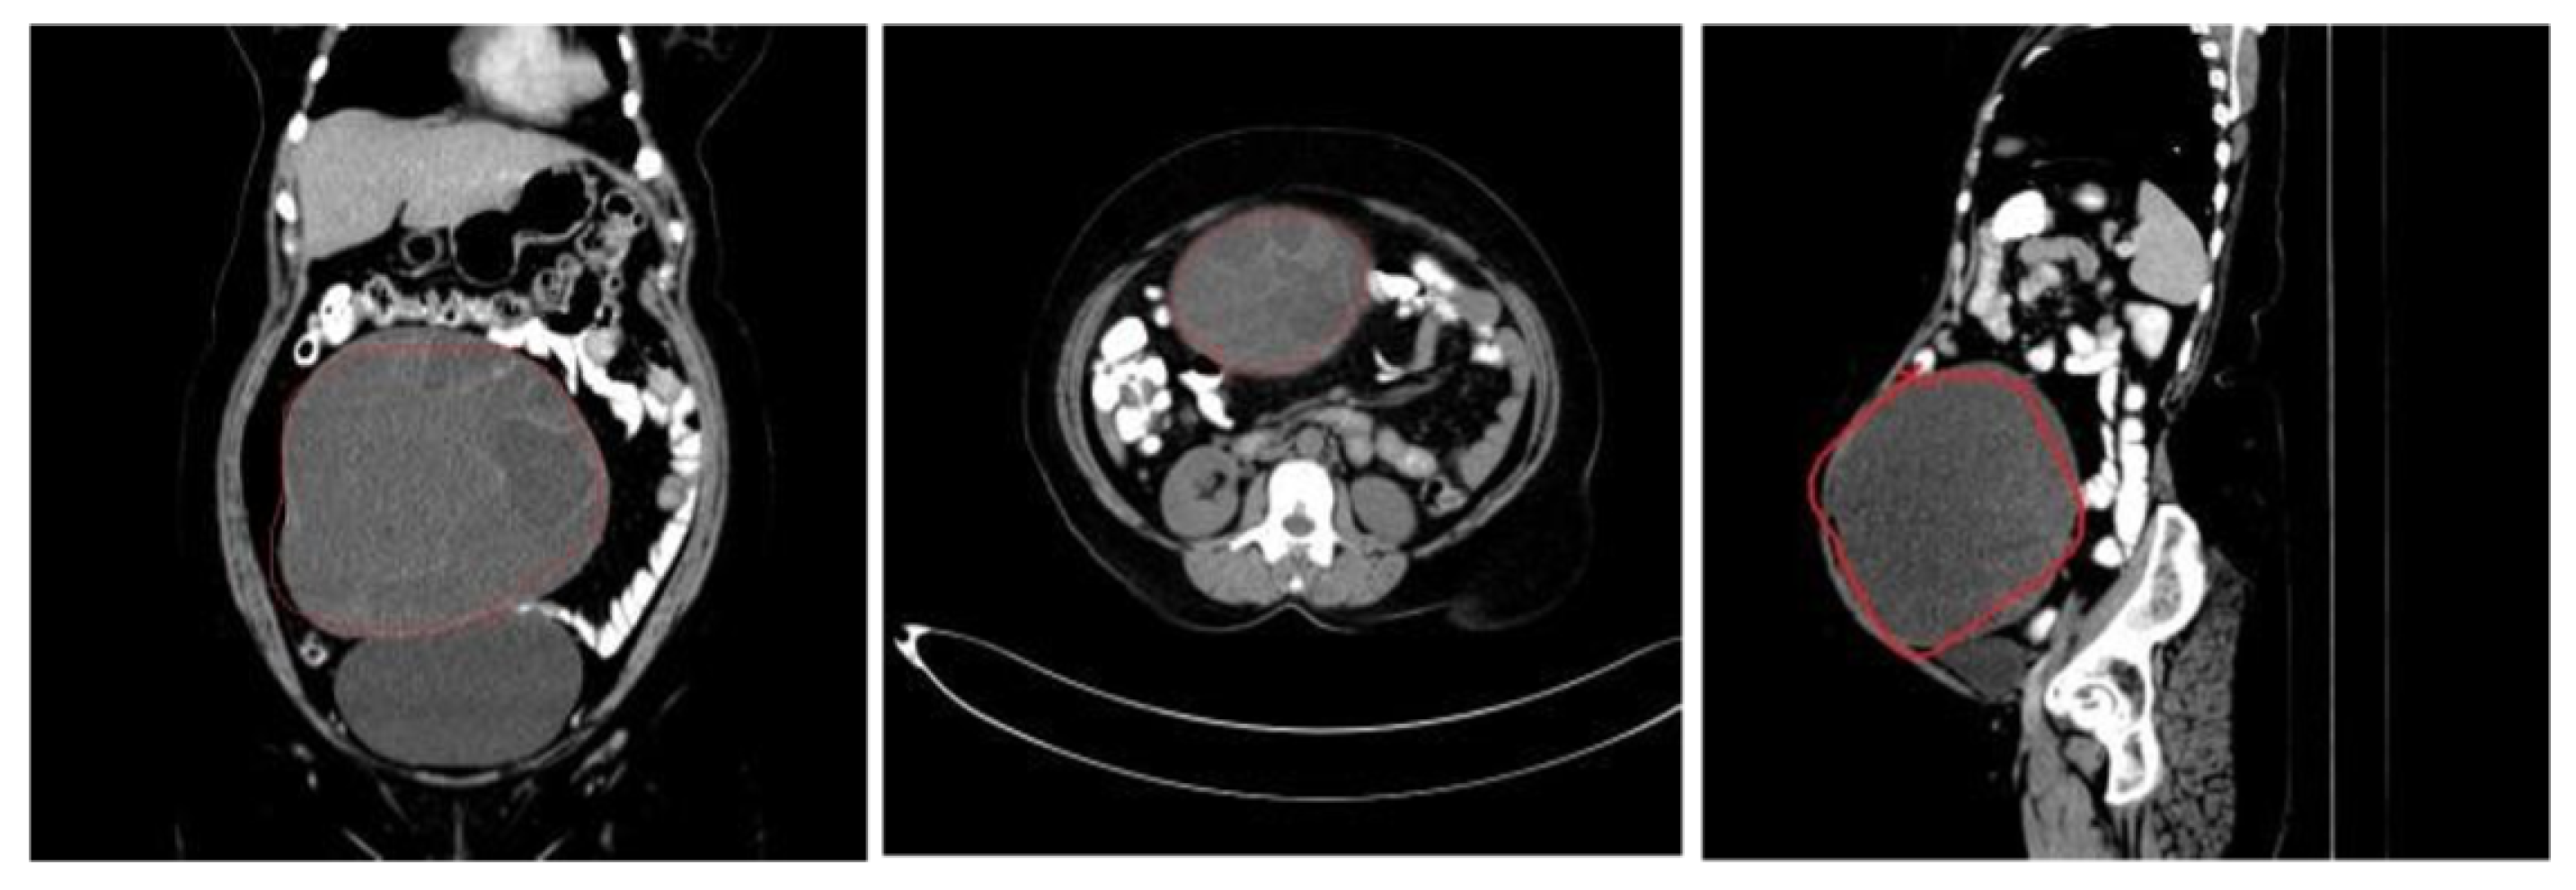

5.1. Data Source and Description

5.2. Data Preprocessing and Dataset Preparation for Training and Evaluation